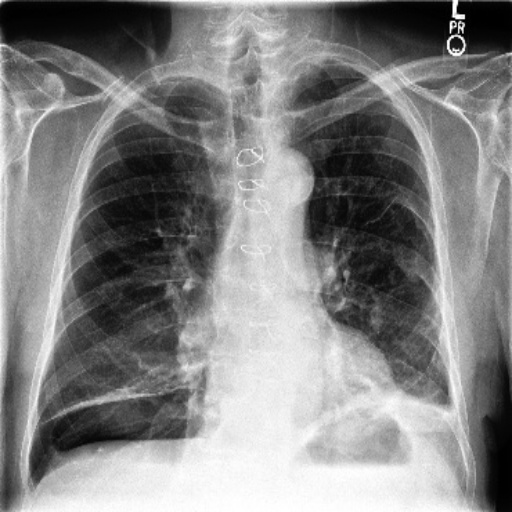

To assess whether dataset-specific signals are present in images independent of pathology, we train a 4-way classifier to predict dataset source (MIMIC-CXR, CheXpert, ChestX-ray14, PadChest). We use DenseNet-161, which achieved the highest internal AUROC and AUPRC in three of the four datasets in our domain shift analysis. Using the strongest-performing architecture ensures that any ability to distinguish dataset sources reflects genuine learnable signatures rather than limitations of model capacity. This DenseNet-161 backbone is trained from scratch on our four training datasets, using only pixel data. Performance is evaluated using Sensitivity, Specificity and F1-Score for each of the four classes (source datasets). As chance-level accuracy is 25%, substantially higher performance would indicate that non-pathological features (e.g., text markers, intensity scaling, acquisition artefacts) allow models to distinguish datasets. Results are shown in Table 5. Example images from each source dataset are shown in Figure 5.

The DenseNet-161 dataset-source classifier achieved near-perfect performance across all four classes (source datasets), far exceeding the 25% chance level. This indicates that public chest radiography datasets contain strong, easily learnable site-specific signatures. which are deeply embedded in the data. These signals are unrelated to pathology and instead likely reflect differences in acquisition protocols, scanner hardware, image post-processing pipelines, or embedded text markers. This finding highlights a critical shortcoming of current public benchmarks - models may exploit non-clinical cues that distinguish datasets rather than learning generalisable representations of disease.

Refer to caption

(a) CheXpert

(b) MIMIC-CXR

(c) ChestX-ray14

(d) PadChest

(e) CheXpert

(f) MIMIC-CXR

(g) ChestX-ray14

(h) PadChest

Figure 5: Example chest radiographs from MIMIC-CXR, CheXpert, ChestX-ray14 and PadChest. Each image contains text artefacts.